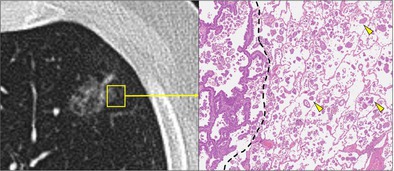

肺叶下切除术在早期肺腺癌的治疗中越来越受欢迎,通常在CT上表现为磨砂玻璃结节。然而,磨砂玻璃结节是一组异质性病变,它们经常被等同于原位或鳞状腺癌。许多病变在组织学上表现为高级别微乳头状分布,并表现为通过空气间隙扩散(STAS);与叶下切除术后复发率增加相关的特征。JCOG0802和CALGB140503试验中STAS影响的事后分析目前正在进行中,尚未发表。这篇简短的报告旨在提高人们对这些相关问题的认识,这些问题在接近早期肺腺癌的管理时应该考虑。

Sublobar resection is gaining popularity for the treatment of early stage lung adenocarcinoma, often presenting as a ground glass nodule on CT. Ground glass nodules are, however, a heterogeneous group of lesions, and they are too often equated with in situ or lepidic pattern adenocarcinoma. Many of these lesions actually harbor high grade micropapillary pattern and display spread through air spaces (STAS) on histology; features that are associated with increased recurrence following sublobar resection. Post hoc analysis of the impact of STAS in the JCOG0802 and CALGB140503 trials is currently ongoing and has yet to be published. This brief report aims to raise awareness of these pertinent issues that should be considered when approaching the management of early stage lung adenocarcinoma.